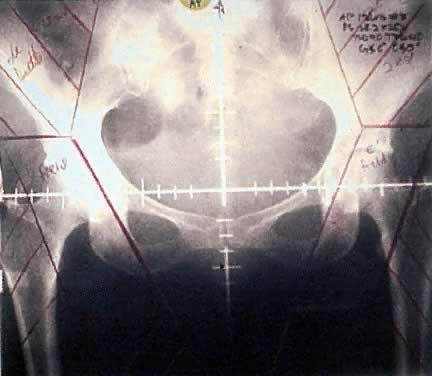

Vulvar tumors require treatment of the primary site as well as draining lymph nodes. Areas at risk for harboring microscopic disease typically receive doses between 45 and 50 Gy, whereas gross disease usually requires doses above 60 Gy. Opposed anteroposterior (AP/PA) treatment fields encompass the pelvic lymph nodes, inguinofemoral lymph nodes and perineum. High-energy beams (10 mV or more) delivered from opposing sides of the target yield a homogeneous dose distribution across wide treatment depths. This characteristic is important because the target volume often lies across several centimeters of tissue, different targets lie at different depths, that is, the groin versus the pelvic lymph nodes, and because the body has a heterogeneous surface. Simulation films used for the treatment of a typical vulvar cancer patient are shown in Figures 3 and 4. The radiation beam can be pictured passing through the plane of the page. The grid marks the central rays of the photon beam and the straight lines at the corners represent the area in the beam's path, which is blocked by Cerrobend, a metal that is liquefied when heated, poured and then allowed to cool in the shape of the area of desired protection. Thus, 1-cm Cerrobend attenuates the radiation beam by 50%. Five to six centimeters of block are required to diminish the radiation dose to less than 5% at the surface of the skin. In the example shown, bowel and soft tissue that are not overlying or underlying targets of interest are blocked out. One structure of concern for radiation damage is the head of the femur. The posterior treatment field shown in Figure 4 does not pass through the femoral heads and therefore excludes the groin, which would be underdosed without a make-up dose from the anterior side. Because the inguinal lymph nodes lie close to the skin surface, treatment of this area with separate electron beams, which deposit more energy near the skin surface compared with photons, allows coverage of the groin while limiting the total dose to the femoral heads. After 45 to 50 Gy is delivered to areas at risk for microscopic disease, the treatment field is reduced to cover only that area of gross tumor that can be marked at the time of initial simulation with a radiopaque wire. Treatment can then proceed to the necessary dose.

Fig. 3. Anteroposterior portal including primary site, pelvic nodes, and groins. Electron fields are shown in purple. This area receives dose contribution from both photons and electrons.

Fig. 4. Posterior simulation film for patient with vulvar cancer. Note that the femoral heads are blocked.